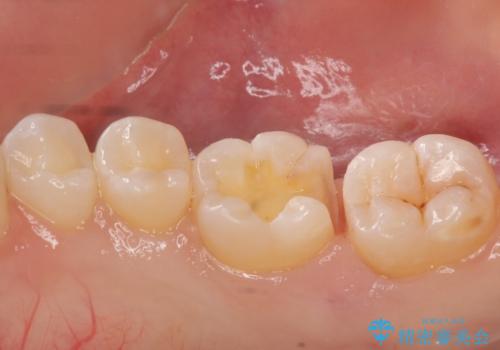

奥歯の虫歯 セラミックインレーによる治療

- 検査をしたところ奥歯に小さな虫歯を発見。

大きくなる前に白い詰め物で治療がしたいとのことでセラミックインレーでの治療になりました。

- 左下6 セラミックインレー 77000円×1本費用は治療当時の料金となります

口の中を見ただけでは異常がないのにレントゲン画像上では虫歯がある、といったことは多々あります。奥歯とはいえ、口をあけると外から見えてしまうため白いセラミックでの治療ができたことを大変喜んでいただけました。